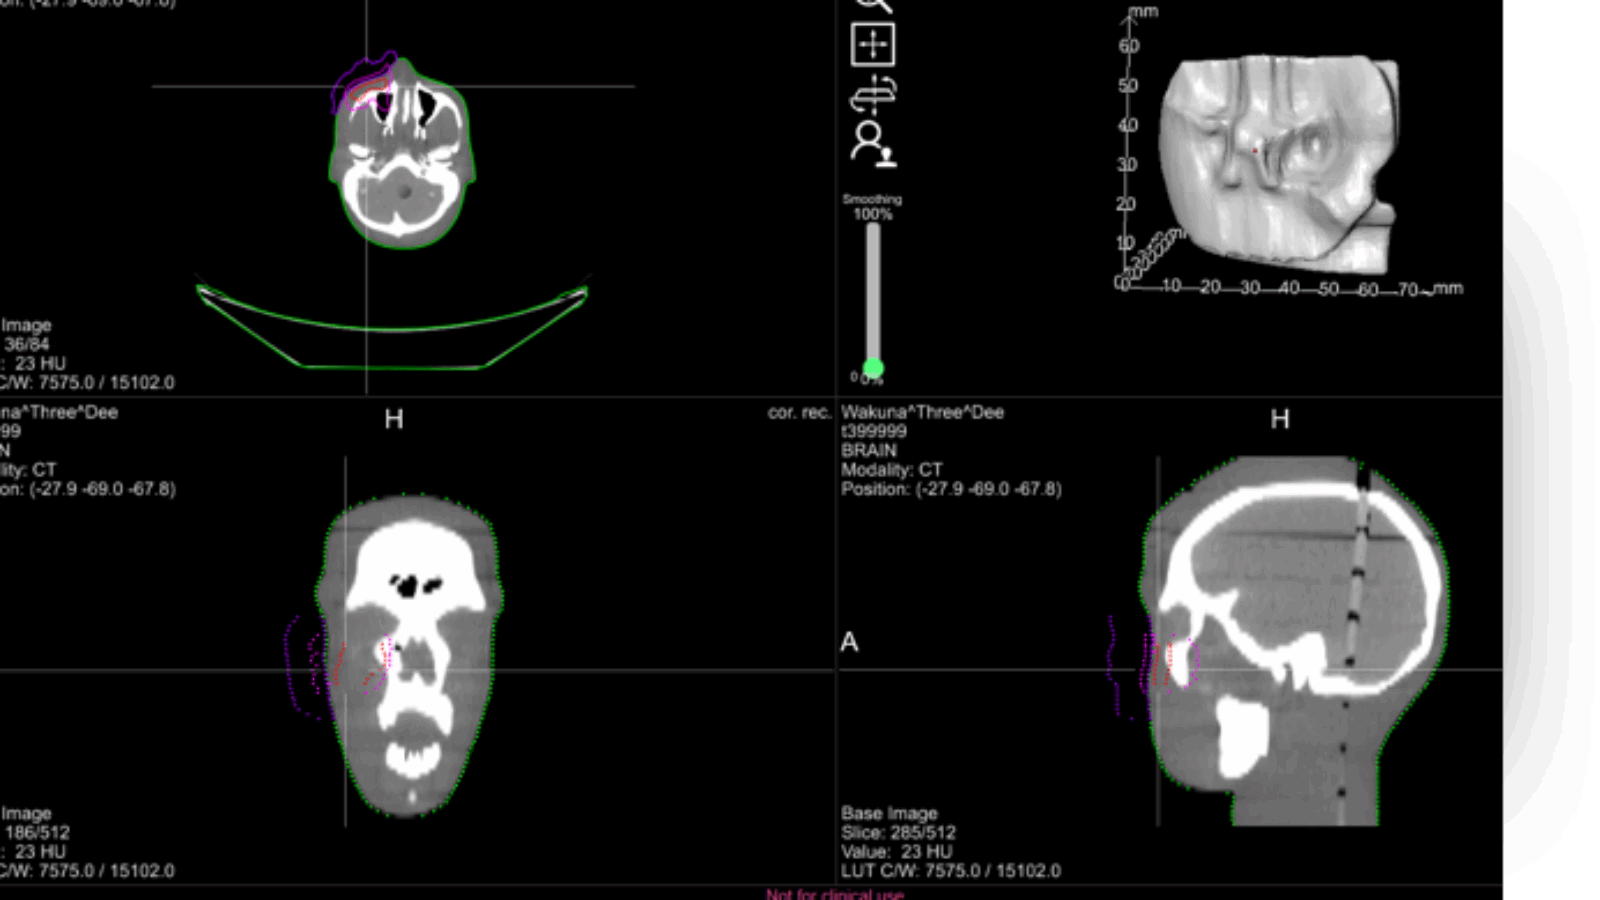

While Adaptiiv has not revealed what the proceeds will be going towards, it is expected that the company will be further developing its proprietary cancer treatment software, which is the spine of its business model. The software converts patients’ CT scans into digital 3D models which are exported as STL files. The models are then 3D printed either by the hospital’s facilities or Adaptiiv’s own facilities if the hospital is lacking a 3D printer. The end result is a bolus that conforms to the patient’s specific individual anatomy.